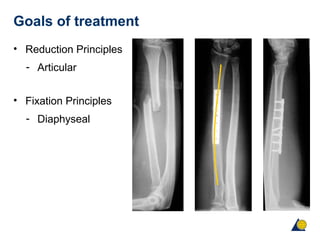

Goals of treatment

• Reduction Principles

- Articular

• Fixation Principles

- Diaphyseal